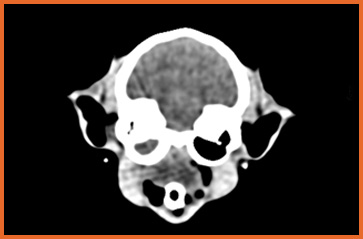

我們提供留院服務並擁有相應的治療設施,亦是小數備有CT電腦掃描及MRI磁力共振等大型醫療儀器的診所及醫院。